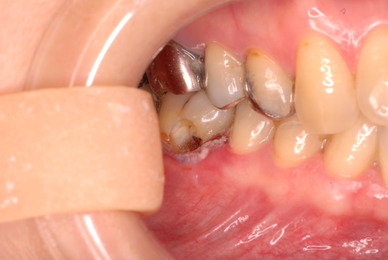

他の都心の矯正歯科で治療中で、ほぼ終了近くの方でした。歯並びで言えば上下の歯が突出していて唇が閉じにくいというのをなんとかしたい。そして歯を抜かないで出来るところを探して都心の矯正歯科への通院となりました。ところが本人曰くよく噛めないというのです。

相談しても“問題無い”の説明だけだそうです。調べたところ歯周病は進行しているし、奥歯の大きい歯2本ずつ計4本はしっかり噛んでいないのです。よく噛めないというのはそのことのようでした。これを矯正的に元に戻すことはできない訳ではありませんが、時間と手間がかかるのは間違いないことです。